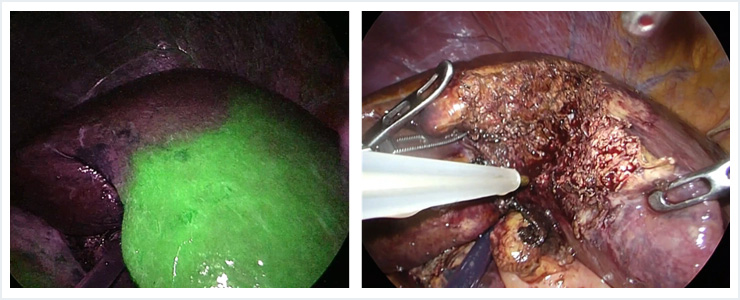

②腹腔鏡下肝切除

腹腔鏡下肝切除は小さな傷で腫瘍を切除することが可能であり、当班では2010年より導入しております。これまでに200例以上に施行していますが、創部痛の軽減のみならず、出血量の軽減、早期の回復がみられ、術後平均在院日数は6日と良好な結果が得られております。比較的シンプルな肝切除から、徐々に複雑な肝切除に適応をひろげており、現在では肝腫瘍の肝切除の70%以上を腹腔鏡で行っております。

またICG蛍光法を用いたナビゲーション手術を導入しており、腫瘍の同定、過不足のない切除範囲の決定に有用です。

【肝細胞癌に対する腹腔鏡下右肝切除とICG蛍光法】